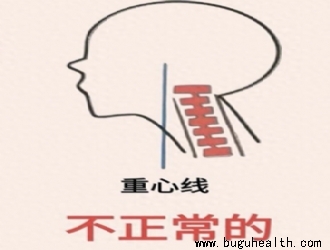

- “收下巴”这个动作,在康复领域通常被称为 “颈椎后缩”(Cervical Retraction),它是几乎所有颈椎康复训练的基石。 头前引姿势是颈椎病中常见的不当姿势――头部的重心在躯干的前侧。它导致颈部和头部的后伸肌组织(斜方肌上部、肩胛提肌、头半棘肌、头夹肌、颈夹肌、枕下肌群)持续收缩,前.....

- 布骨康复医学科普:颈椎曲度变直:成因、影响与应对之策 BuGuHealth ,2024-12-25

- 在现代生活中,颈椎曲度变直的现象却愈发普遍,给人们的健康带来诸多困扰。 颈椎曲度变直的形成与多种因素密切相关。长期不良的姿势堪称“罪魁祸首”之一。.....